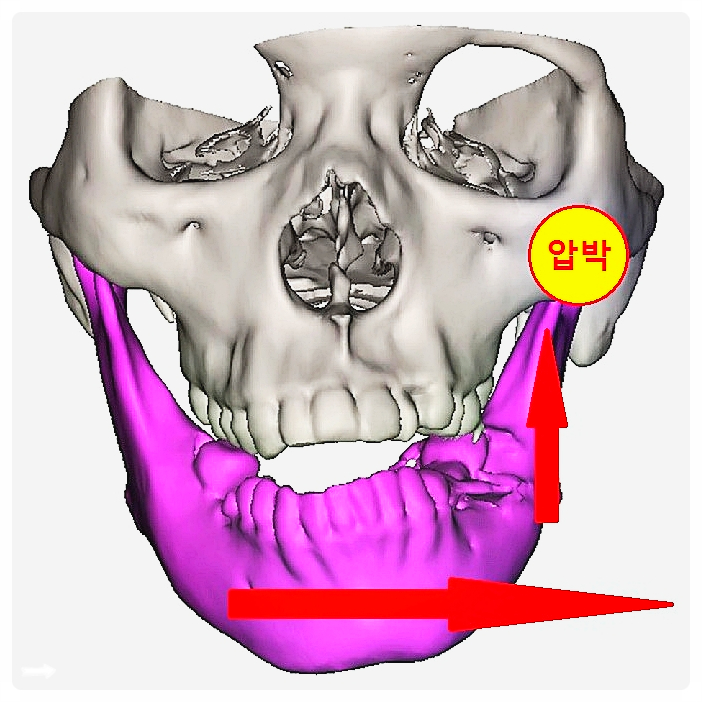

하지만 반복되는 자세와 습관 때문에 턱 주변 근육이 한쪽으로 긴장하면, 장시간 유지되면서 얼굴형 변화가 나타날 수 있습니다.

예를 들어 한쪽으로 수면 자세를 고정하면 밤새 한쪽 관절에 압력이 집중되고, 근육 사용 패턴이 바뀌어 얼굴 비대칭이 뚜렷해지는 경우가 종종 있습니다.

예를 들어 턱을 여닫을 때 좌우 움직임이 다르면, 주변 근육 긴장이 한쪽으로 과하게 몰린 상태일 수 있습니다.

고개가 앞으로 나오는 자세가 반복되면 턱이 자연스럽게 뒤로 밀리면서 관절에 부담이 생깁니다.

즉, ‘턱만 교정’이 아니라, 몸 전체 균형 속에서 턱 위치가 안정되도록 돕는 과정이라고 이해하시면 됩니다.